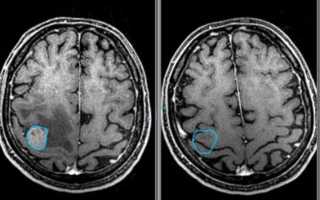

В неясных ситуациях применяется МРТ (магнитно-резонансная томография). В отличие от КТ (компьютерной томографии) метод не несет лучевой рентгеновской нагрузки и может быть применен даже в III триместре беременности. Но из-за технической сложности у грудных (и до 6 – 7 лет) детей способ выполняется только под наркозом и имеет ряд противопоказаний. Данная процедура входит в план обследования при подготовке к хирургическому лечению.

УЗИ головного мозга информативно только на первом году жизни ребенка, до зарастания родничка (подробнее в статье: когда и как зарастает темечко у ребенка?). Его назначают недоношенным детям, а также перенесшим кислородное голодание и тяжелые роды. Детям старше одного года и взрослым проводят МРТ. Эти методы дифференцируют кисту и псевдокисту.

В случае выявления образования невропатолог назначает пациенту повторное обследование, для того чтобы определить растет оно или нет. Если ко второму визиту к врачу киста осталась прежних размеров или увеличилась, младенцу назначается терапия, которая призвана предотвратить появления головной боли и судорог. В старшем возрасте псевдокиста исследуется при помощи МРТ и КТ. Благодаря этим исследованиям удается удостовериться в отсутствии опухоли.